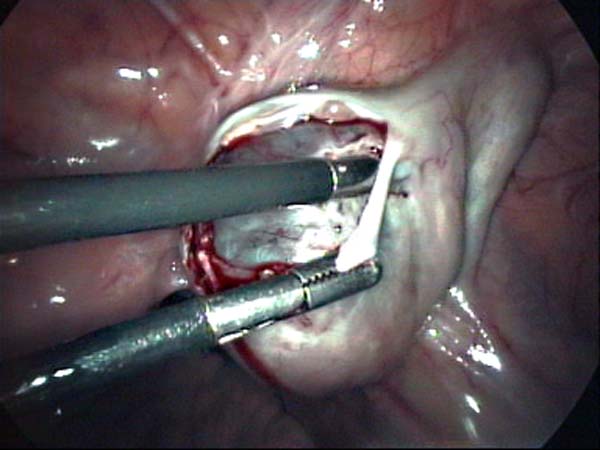

Laparoscopy Photos Ovarian Cyst Ovarian Cystectomy Uterine Septum Tubal Pregnancy